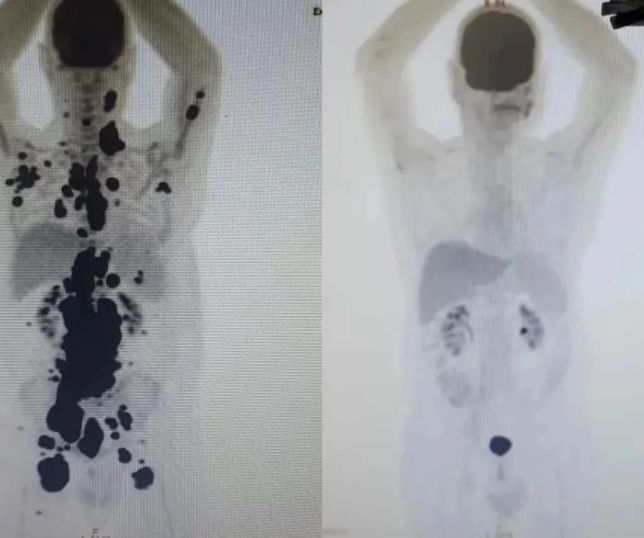

Durante esse período, o grupo focou em eixos prioritários que estão entre as principais necessidades do sistema público de saúde, para garantir a sustentabilidade do SUS. Uma das prioridades é o reforço na produção de insumos que auxiliem na prevenção, diagnóstico e tratamento de doenças determinadas socialmente, como tuberculose, doença de Chagas, hepatites virais, HIV. Mas a iniciativa conta também com investimento no enfrentamento de agravos relevantes para a saúde pública, como doenças crônicas (câncer, cardiovasculares, diabetes e imunológicas), dengue, emergências sanitárias e traumas ortopédicos.